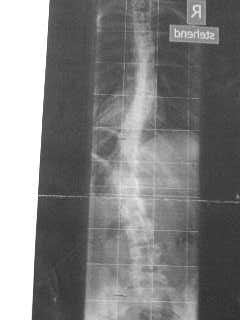

kann mir jemand vielleicht sagen, wie viel grad ich habe?

ich habs vergessen und selbst ausmessen kann ich leider nicht.

es ist eine kopie, leider schlechte qualität

DSC01882.JPG (9.89 KiB) 3156 mal betrachtet

die Bildqualität ist zu schlecht für eine Vermessung, da man die Konturen der Wirbel nicht richtig erkennen kann.

Eine Winkelbestimmung anhand des zu erkennenden Wirbelsäulenverlaufes ergibt ganz grob ca 22° bzw 33° bei den Hauptkrümmungen.

Ist bei dem Bild aber nur ganz grob.

in Deinen Beiträgen schreibst Du doch, dass Du 38 Grad hast.

Achso, danke. Ja 38° ist schon länger her, diese Kopie ist neuer.